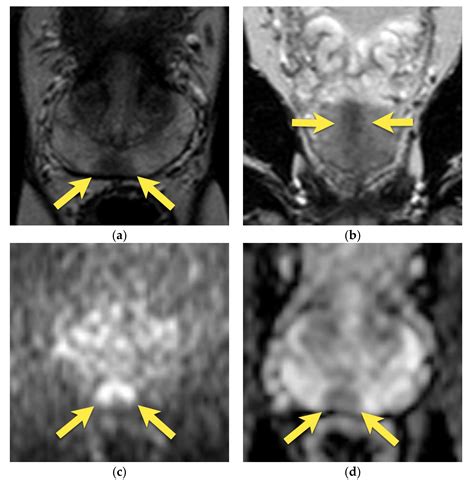

The diagnostic process typically involves three specific sequences that make up the "multi-parametric" aspect of the scan:

• T2-Weighted Imaging: Provides high-resolution anatomical details of the prostate structure.

• Diffusion-Weighted Imaging (DWI): Measures the movement of water molecules in the tissue, which is often restricted in malignant tumors.

• Dynamic Contrast-Enhanced (DCE) Imaging: Monitors how a contrast agent flows into the tissue, helping to highlight areas with abnormal blood vessel growth typical of cancer.